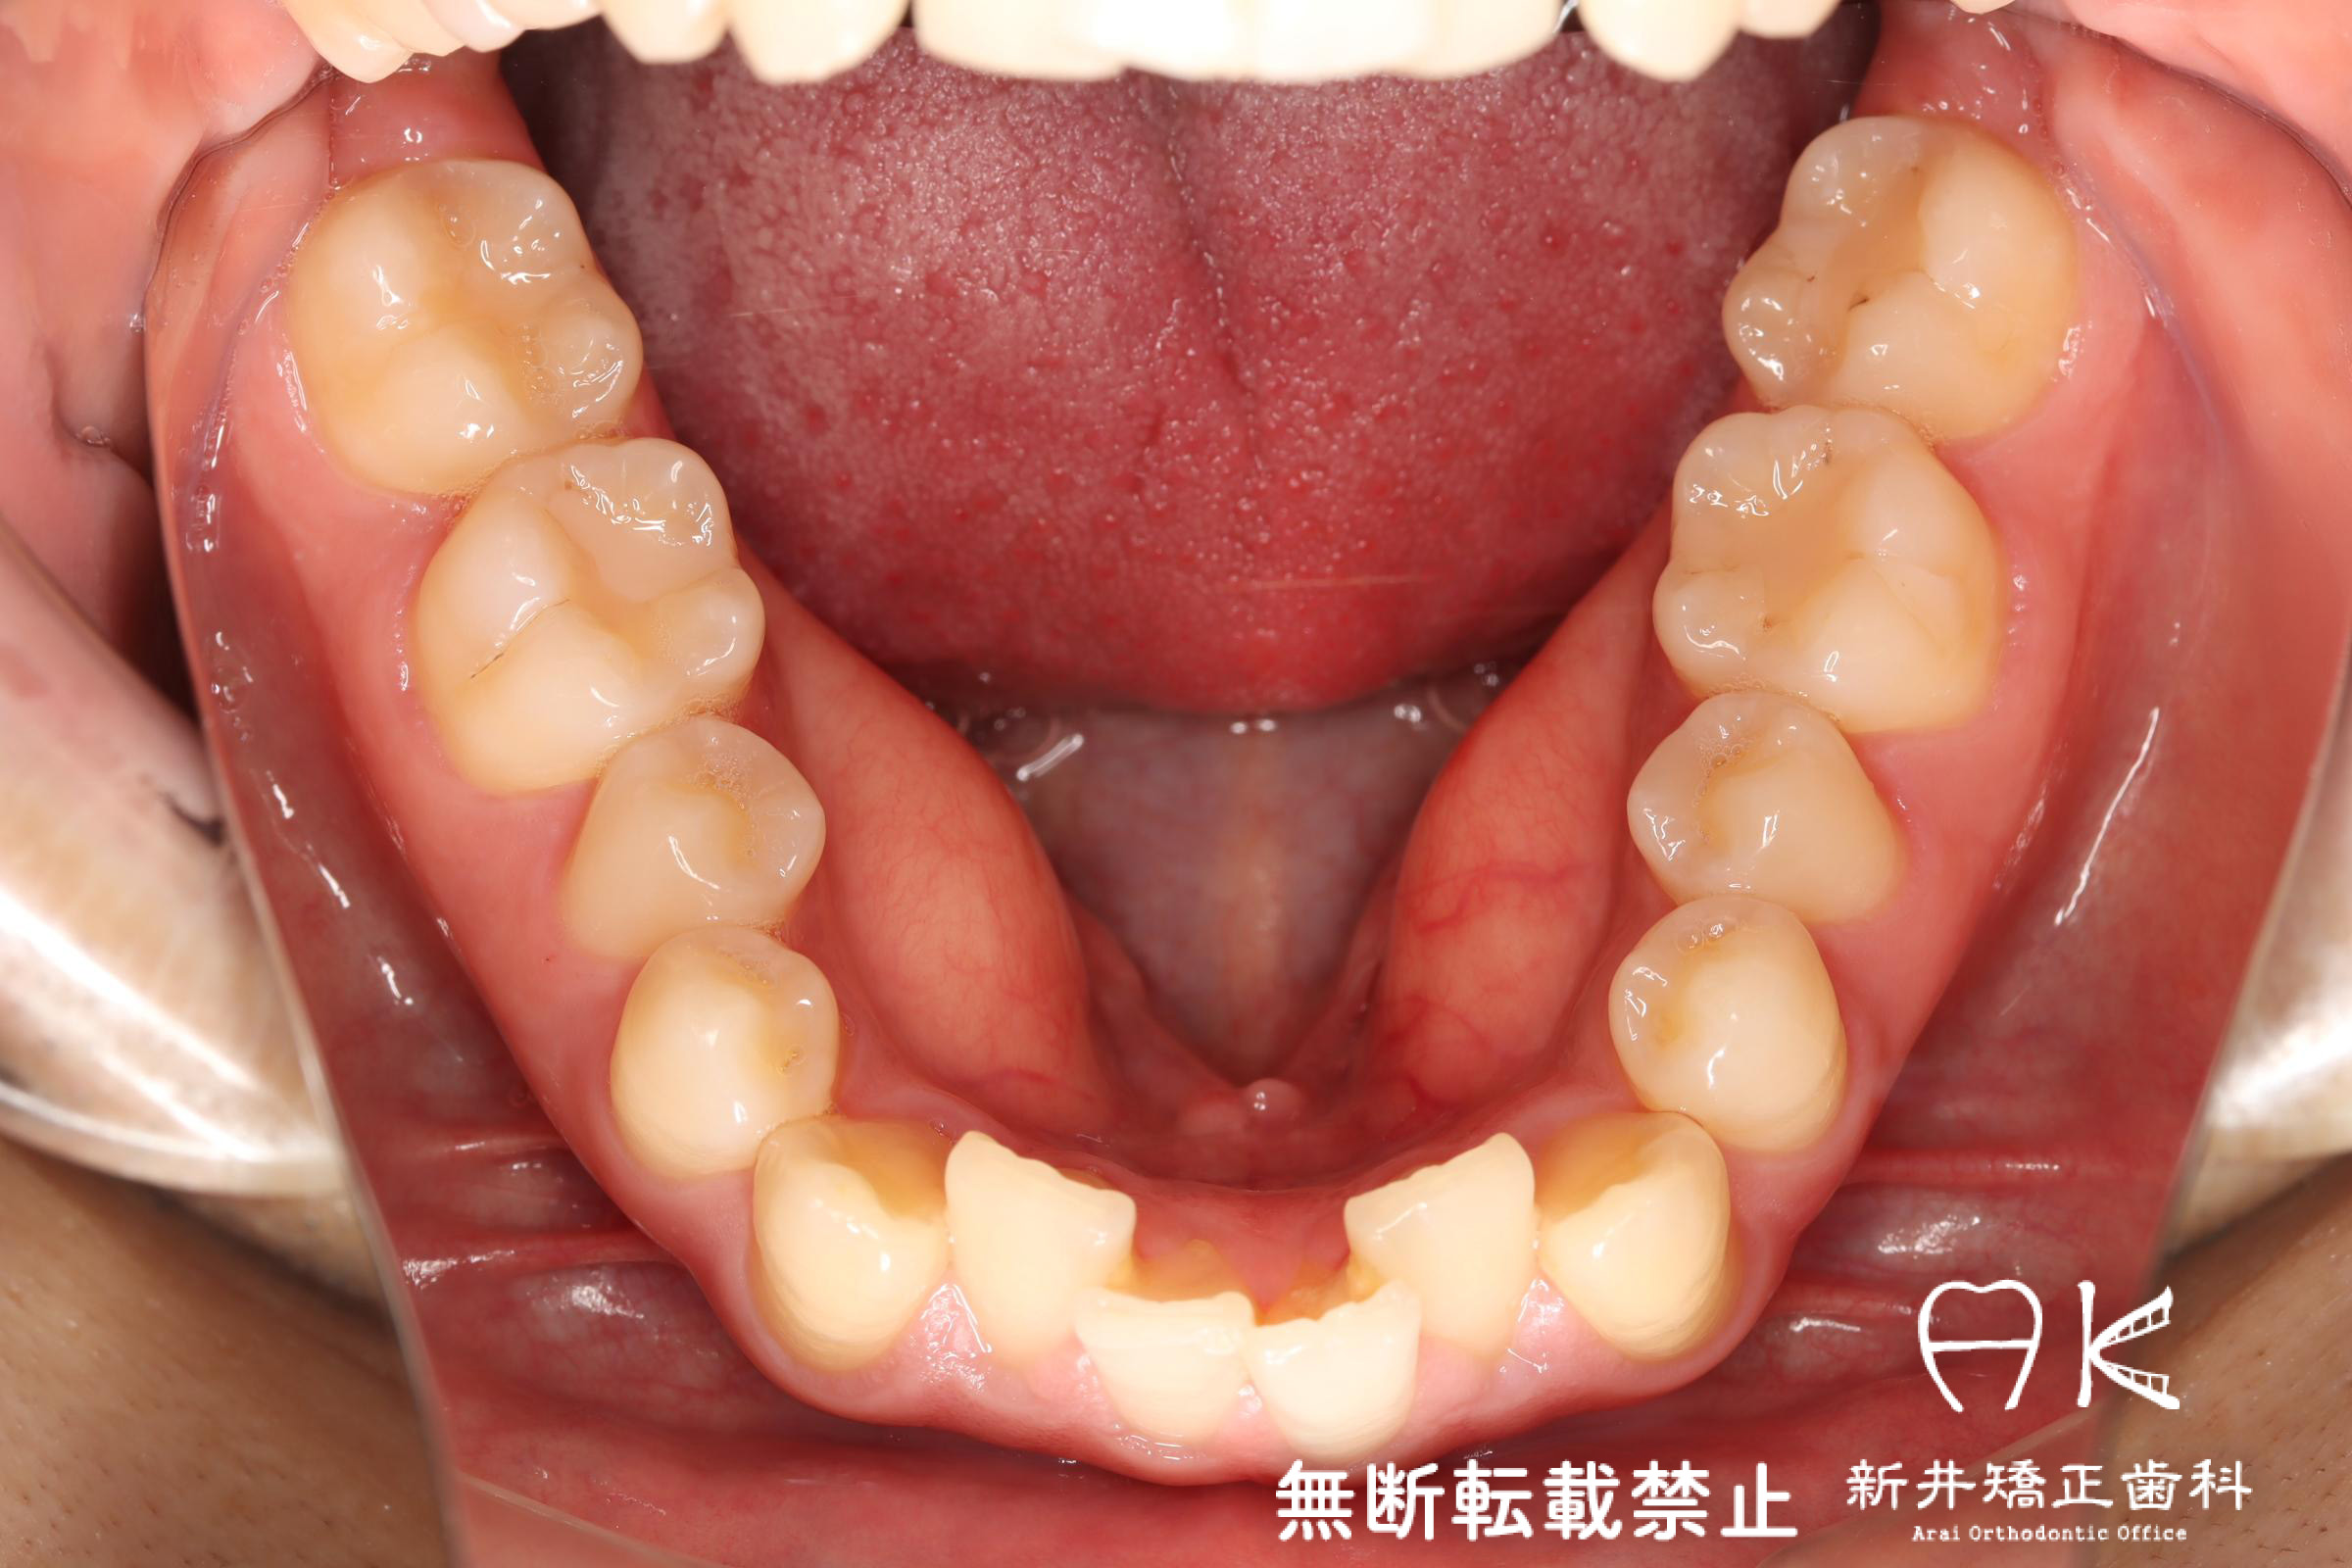

治療前後の解説

| 治療前 | 歯のでこぼこ(叢生)が強く、歯磨きのやりにくい状態の患者さんです。 奥歯(臼歯)のバランスが受け口傾向であったため、顎間ゴムの使用によりかみ合わせのバランスを整えました。 |

| 症状・診断名 | 叢生 |

| 年齢(初診時)・性別 | 20代・男性・立川市 |

| 抜歯の有無 | 非抜歯 |

| 使用矯正装置 | マウスピース型矯正装置(インビザライン) |